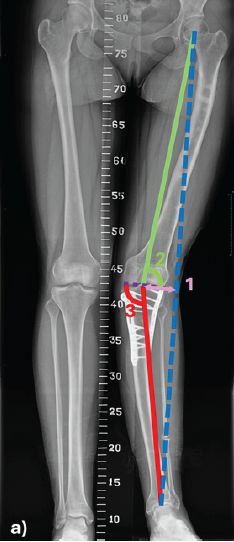

Repeated Surgeries and Clinical Assessment Using 3D Gait Analysis in Unilateral Congenital Short Femur: A Case Report

Hiroki Fujita , Yutaka Kozakai , Misa Kaga , Junya Shimizu , Atsushi Teramoto